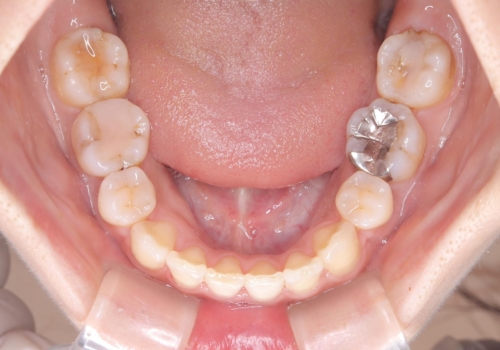

- 主訴:口元を下げて前突感を無くしたい、下の歯の凹凸も無くしたい

右側第二小臼歯、左側第一小臼歯、下顎両側第一大臼歯を抜歯しワイヤ-矯正を行いました。

骨格的顎の変位を認めたため、顔貌に対しピッタリ上下の歯の正中を合わせることは難しいと説明し、上下左右計4本小臼歯を抜歯しワイヤー矯正治療を行いました。